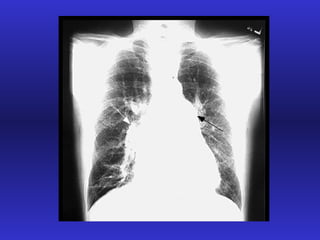

Exacerbación de la EPOC Paradigma de la IR aguda sobre crónica

Progresión de la EPOC Injuria Tabaco, polución Clearence  mucociliar Colonización bacteriana Mediadores bacterianos Daño vía aérea Respuesta inflamatoria PMN citoquinas

Insuficiencia respiratoria crónica

Factores pronósticos en IR crónica Persistencia de hábito tabáquico Cor Pulmonale: Hipoxemia  Acidosis Policitemia Pérdida del lecho vascular pulmonar VEF 1 Comorbilidad